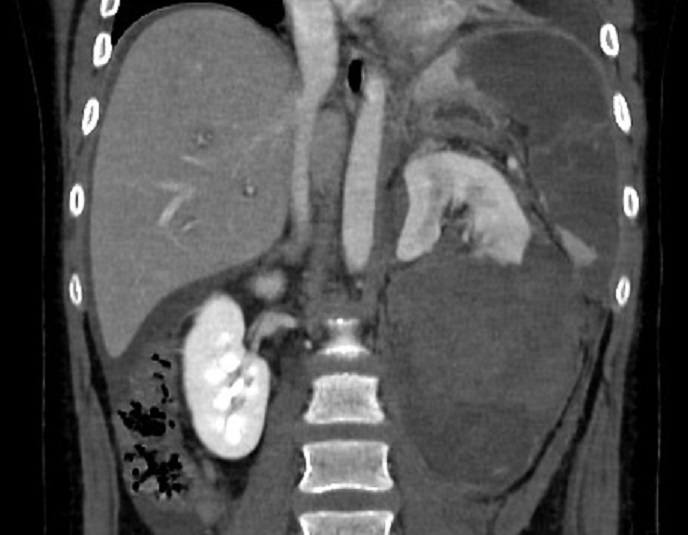

Image

radiologique TDM d'une hematome sous capsuilaire de

la rate avec aspect de croissant hypodensite

soucapsulaire de la rate ( fleche blanche superieure

) . Coupe TDM axiale avec contrast intraveineuse

temps veineuse . |

|

Image radiologique de laceration de la rate, le rein et du

foie . Aspect radiologique de laceration est ligne hypodense

peut en s'observe sur la rate , le rein et fu foie ..

Rein gauche est tres voluneuse Coupe TDM

coronal de l'abdomen au temps veineuse |